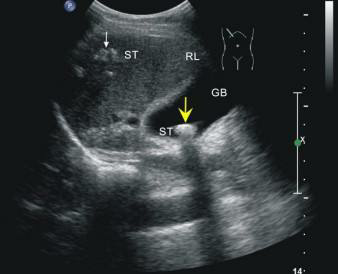

這位先生姓錢,自訴飲酒后出現(xiàn)胸骨后疼痛4小時(shí),呈壓榨性,持續(xù)不緩解,伴大汗、面色蒼白、惡心、欲吐,既往無高血壓、糖尿病、冠心病病史,吸煙史30年,偶有飲酒,入院時(shí)查體血壓為120/80mmHg,心率:98次/分,節(jié)律規(guī)整,未聞及明顯雜音。心電圖:竇性心律,心率98次/分,II、III、aVF導(dǎo)聯(lián)病理性Q波,ST段下移,不正常心電圖。不除外急性心肌梗死。急檢心肌酶及超敏肌鈣蛋白、淀粉酶,結(jié)果回報(bào)心肌酶、超敏肌鈣蛋白無明顯改變。疼痛時(shí)復(fù)查心電圖較前無變。胸痛癥狀仍持續(xù)不緩解,給予曲馬多止痛不改善。請示李桂武主任醫(yī)師,主任給予詳細(xì)詢問病史、癥狀及查體,患者膽囊區(qū)有壓痛無反跳痛,考慮患者可能存在膽囊性疾病,不排除腎結(jié)石,指示:急檢肝膽胰脾彩超及泌尿系彩超。我急忙陪著患者及家屬去門診彩超室做肝膽胰脾及泌尿系彩超。結(jié)果如下圖。提示膽囊結(jié)石。

請肝膽外科梁博主任會(huì)診后建議行CT檢查以進(jìn)一步明確診斷,肝膽胰脾CT結(jié)果可見膽囊不大,內(nèi)見高密度結(jié)節(jié),約10mm(IM33),膽總管無擴(kuò)張。建議轉(zhuǎn)入肝膽外科行手術(shù)治療。